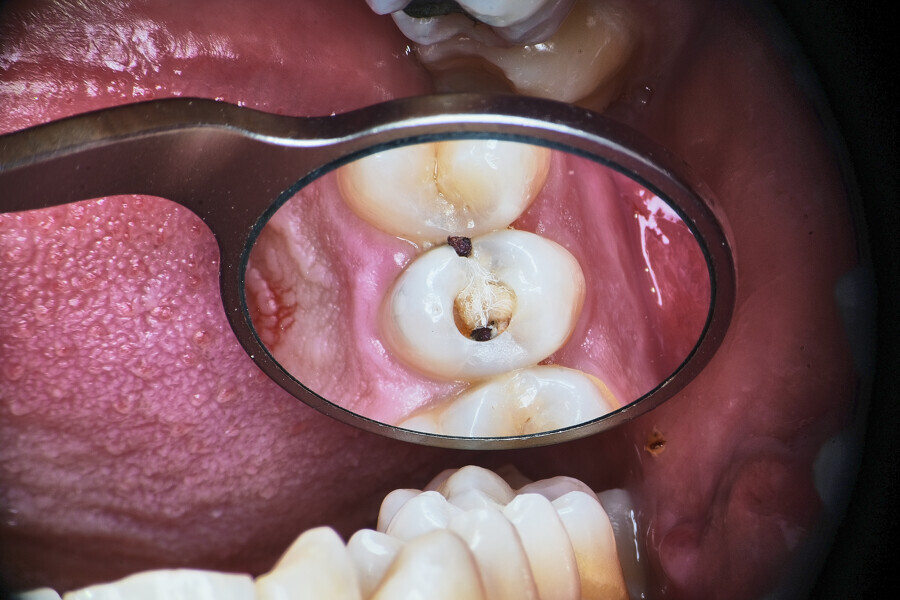

Fig. 1.

The piston technique is simple and predictable. Once the final preparation and irrigation protocol has been performed, owing to the specific properties of CSBSs, the canal should not be overdried. A small amount of moisture should remain in the canal space as the catalyst for the setting reaction of the sealer. With the application needle introduced to the maximum level of the insertion, gently eject the material from the syringe directly into the canal space. To avoid extrusion, try not to block the needle in the canal. After seeing the material in the canal space, remove the needle and use a hot gutta-percha extruder to create a plug in the coronal part. Next, push the coronal part of the gutta-percha with the cold plugger towards the apical zone. Do not push more than 1–2 mm (Fig. 1).